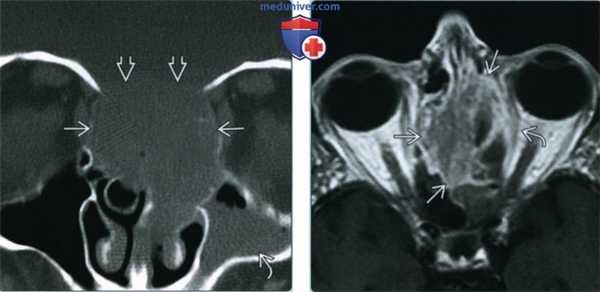

(Слева) При корональной «костной» КТ определяется большое объемное образование в верхних отделах полости носа с обеих сторон с двухсторонним поражением решетчатого лабиринта. Определяется агрессивная деструкция костей с эрозией перегородок решетчатого лабиринта и передних отделов основания черепа. В левой верхнечелюстной пазухе определяется «запертый» секрет.

(Справа) При аксиальной MPT, Т1ВИ С+ у этого же пациент: определяется диффузное неоднородное контрастное усиление СННР, оказывающею объемное воздействие на структуры левой орбиты с выбуханием кнаружи внутренней прямой мышцы.

2. КТ при синоназальном нейроэндокринном раке:

• КТ с КУ:

о Мягкотканная опухоль с вариабельным контрастированием, нечеткими краями и инвазией окружающих структур

• «Костная» КТ:

о Агрессивная деструкция костей

3. МРТ при синоназальном нейроэндокринном раке:

• Т1 ВИ:

о Плохо отграниченное мягкотканное образование, изоинтенсивное мышцам

• STIR:

о Неоднородный, гипоинтенсивный или промежуточный длительный TR сигнал

• T1 BИ C+ FS:

о Вариабельное, обычно диффузное контрастирование